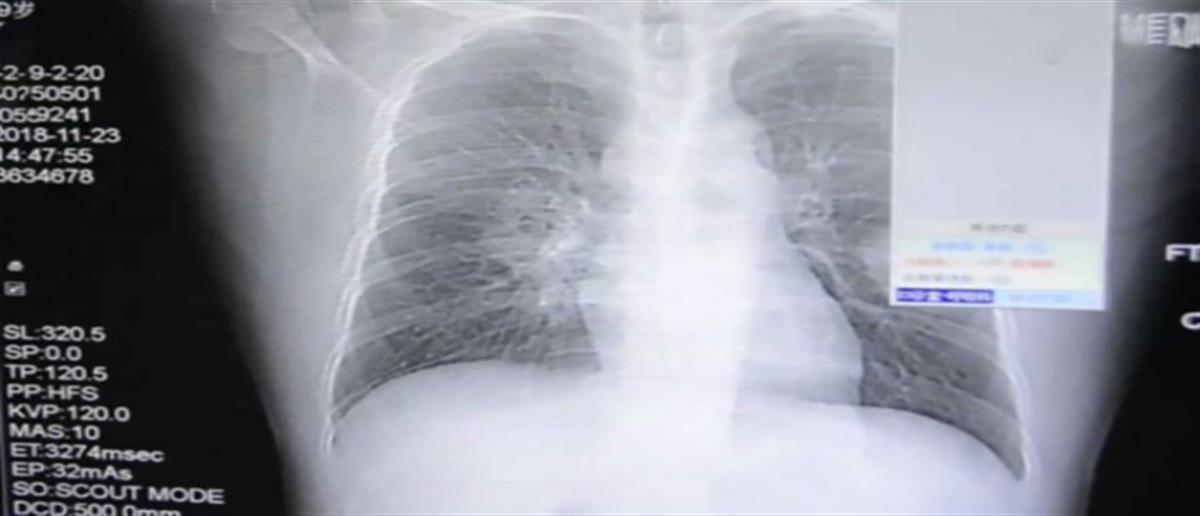

Ένας άντρας, από την επαρχία Fujian νοσηλεύτηκε καθώς υπέστη σοβαρή μυκητιακή λοίμωξη στους πνεύμονες, η οποία φέρεται να προκλήθηκε από την κακή συνήθειά του να μυρίζει τις κάλτσες του κάθε βράδυ.

Σύμφωνα με δημοσιεύματα, όπως αναφέρει το ladbible, η αυτή συνήθειά του είχε ως αποτέλεσμα να προσβληθεί από μύκητα, ο οποίος δημιούργησε πρόβλημα στους πνεύμονές του, αναπτύσσοντας σπόρους.